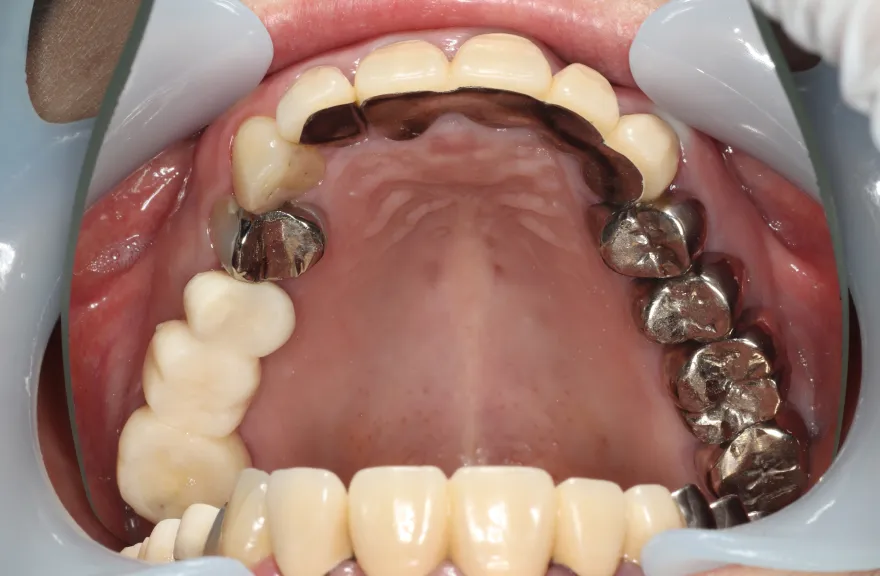

骨格の前後的な差がある方でした。術前のレントゲンより、上下で歯牙の損傷に明らかな差があるのがみてとれます。

上の歯がないところにインプラント治療を行い、上顎は全てインプラントフィクスチャーによる固定性の歯を入れられることも費用的には可能な方でした。

今回の症例では、敢えて上顎は総義歯形態をとり、骨格的な前後の差を解消するよう工夫しました。

上顎の残っていた歯も、差し歯としては使えずとも、敢えて根だけ残すことによって組織を温存し、義歯の安定に寄与するよう設計しました。